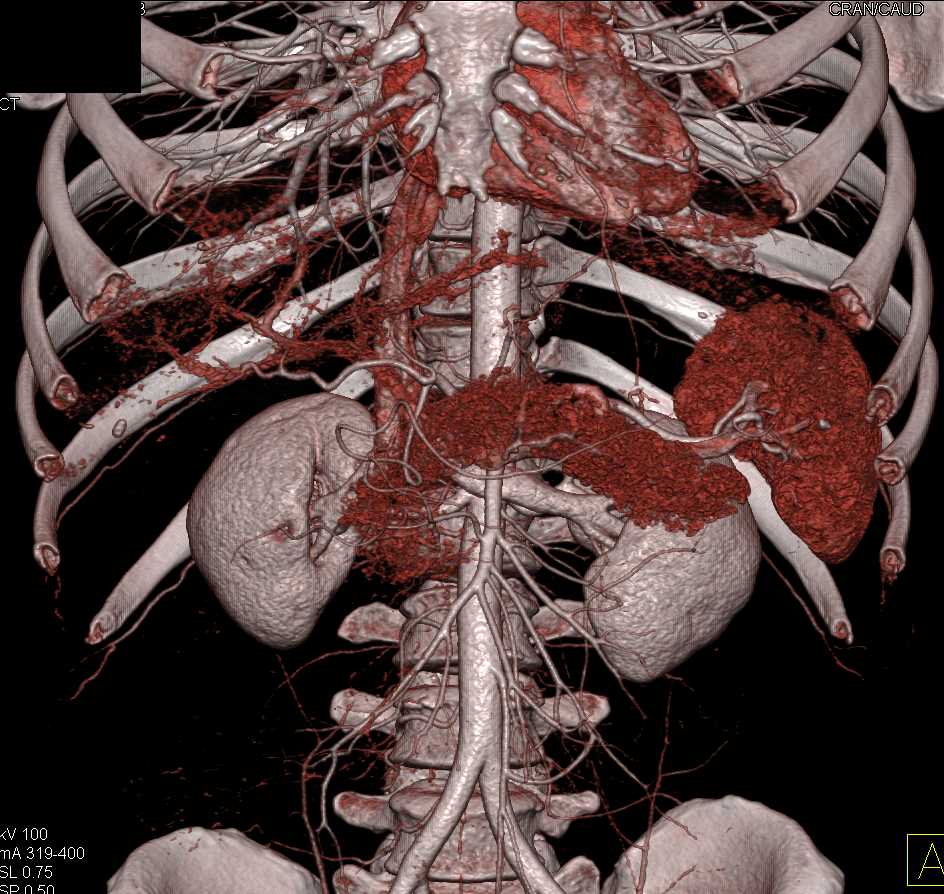

Neuroendocrine Tumor Body of Pancreas